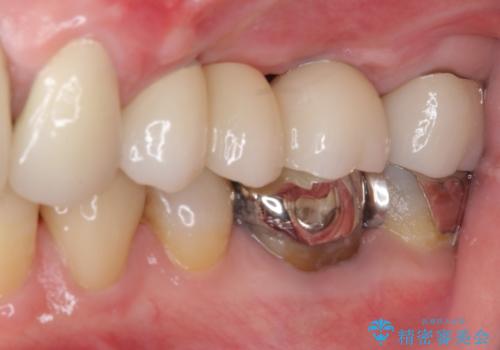

ブリッジの土台が割れて痛い インプラントによる補綴治療

- 上の奥歯に装着されているブリッジが痛むとのことで来院された患者様です。

診察した結果、ブリッジの土台となっている歯が割れていたため、抜歯が必要となりました。

欠損している歯数が多いため、ブリッジによる補綴治療は困難と判断し、インプラントによる補綴治療を行うこととしました。

インプラントを埋入するために必要な骨の高さがなかったため、上顎洞底の粘膜を挙上しました。

手術後は処置部に痣や腫脹が出現したり、痛みが出たりしましたが、補綴治療後は咬み合わせが安定し、大変満足していただきました。